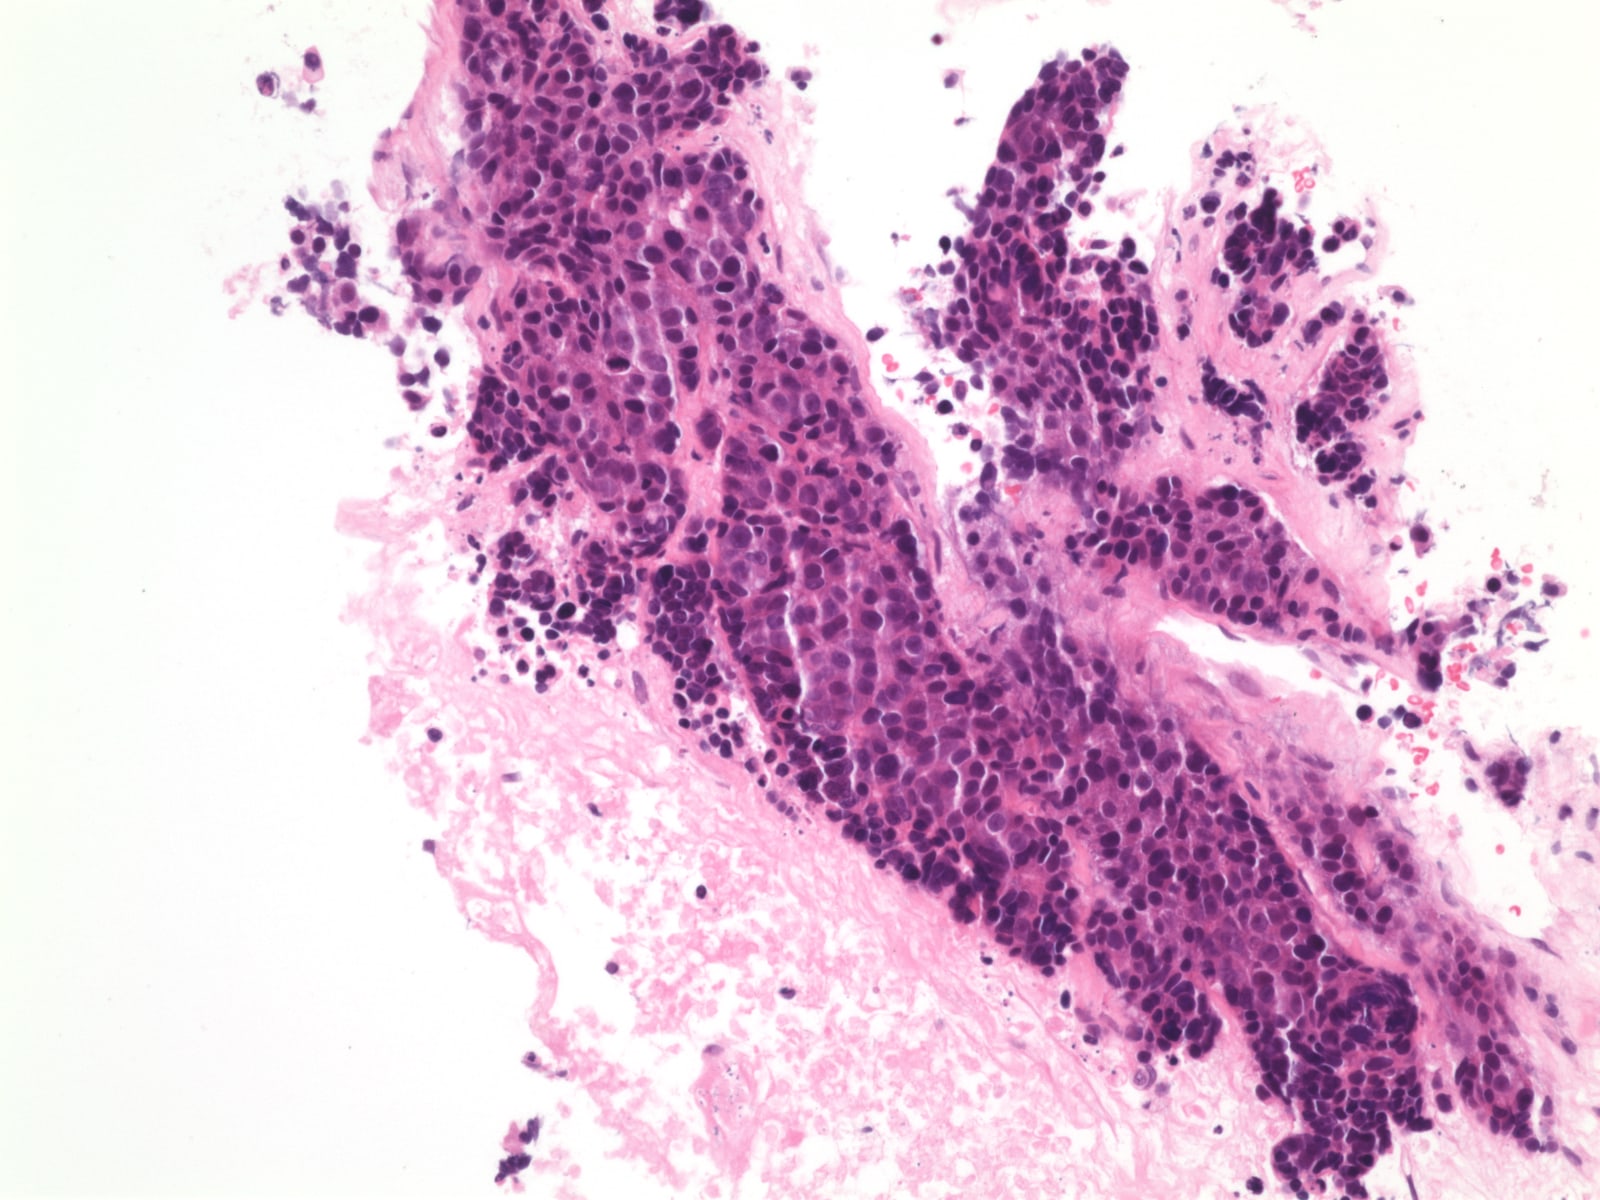

Microscopic images of thymic hyperplasia great lymphoid follicles ((a Thymic Hyperplasia Pathology Outlines True thymic hyperplasia is defined as increase in both size and weight of the gland while maintaining normal architecture. Defined as the presence of lymphoid follicles in the thymus regardless of the gland size. 65% of patients have thymic hyperplasia, 25% normal thymus, 10% thymomas; Risk factors for thymoma are males with initial. In fact, the gland is of normal. Thymic Hyperplasia Pathology Outlines.